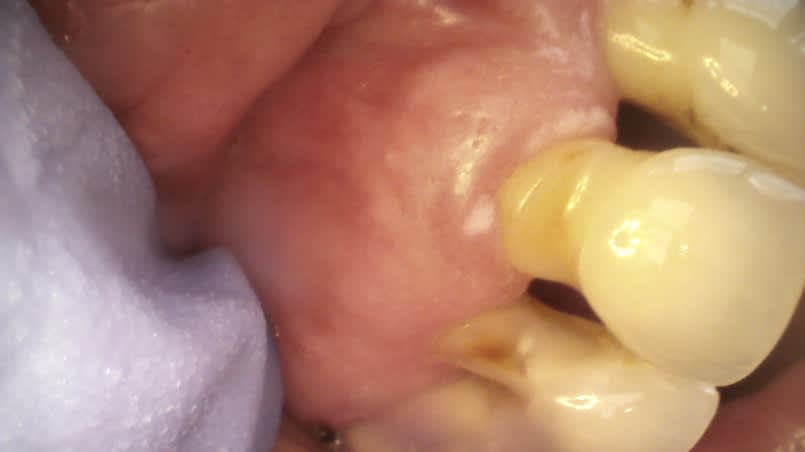

J'ai reçu une patiente hier qui présente depuis 1 mois environ une petite plaque et un point kératosique au niveau du collet de sa 21.

Je n'arrive pas à éliminer cette plaque au grattage, pas hémorragique, légère induration de cette zone.

En fait c'est localisé sur la 11, oups!

Ce dont je parle est ce petit liseré blanc en mesial de 11 et la petite tâche blanche à la limite du sulcus en vestibulaire.

C’est bizarre ses collets tout concaves.

Keratose traumatique cause brossage.

Kératose chimique ? Cause reflux ?